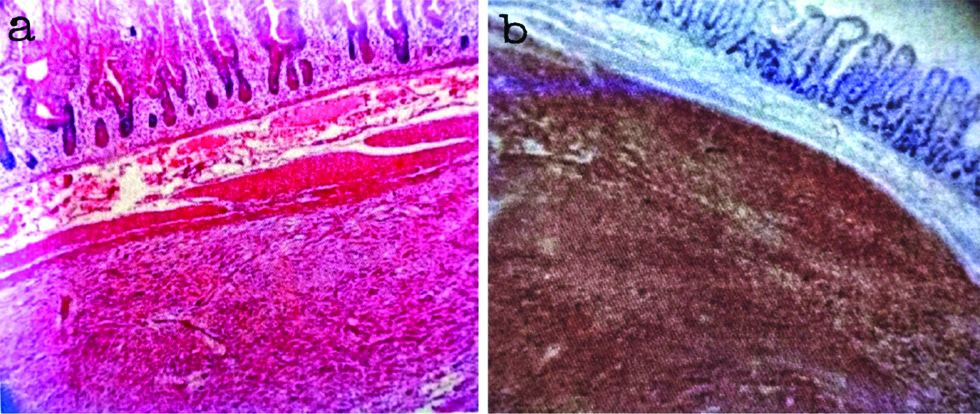

Immunohistochemical markers used to confirm the histopathological diagnosis in this study included CD117, DOG-1 and Desmin. CD117 is considered as a good diagnostic marker of GIST’s. The staining patterns of CD117 in GISTs can be diverse and includes cytoplasmic, membrane and paranuclear or golgi pattern, even though CD117 is very useful in the diagnosis. 5-10% of GISTs are CD117 negative. On immunohistochemical analysis 90 cases (83.3%) cases showed positivity for CD 117, 96 cases (88.9%) cases were positive for DOG-1 and all the 108 cases (100%) cases were negative for Desmin [Table/Fig-4]. Desmin was used to exclude the smooth muscle neoplasms and all 108 cases included in this study was negative for desmin. The sensitivity and accuracy of CD117 was 83.3%, positive predictive value was 100% and false negative value was 16.7. When CD 117 and DOG-1 were compared, DOG-1 was found to be more sensitive and accurate (88.9%), with a positive predictive value of 100% and a false negative value of 11.1.

a) Microphotograph depicting spindle cell GIST (H&E, X 400); b) Desmin negativity in spindle cell GIST (Desmin, X 400).

The accuracy and sensitivity of CD117 and DOG-1 in the present study which correlated with the observations of Krishnappa P et al., and Sun XW et al., respectively [21,22]. Present study results of DOG-1 positivity in CD117 negative GIST are almost similar to the findings of Lee C et al., [Table/Fig-6,7] [23].

a) Microphotograph depicting submucosal location of GIST (H&E, X 100); b) DOG-1 positivity in the submucosal lesion (DOG-1, X 100).